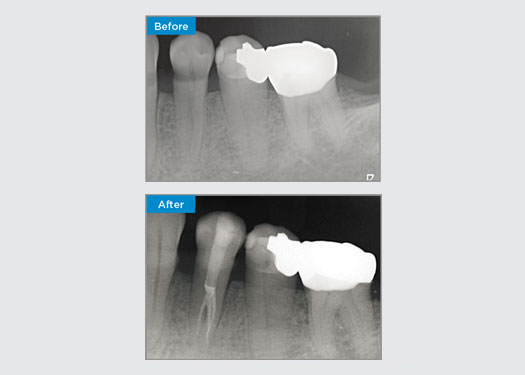

The patient presented with asymptomatic apical periodontitis on tooth 34. From the pre-op radiograph, tooth 34 was noted with two visible roots. However, a CBCT scan confirmed a three rooted premolar, and the canals divided into three at the mid root. A careful file selection is critical for this delicate tooth.

Dr Jack Lin, Endodontist, Sydney, NSW Australia